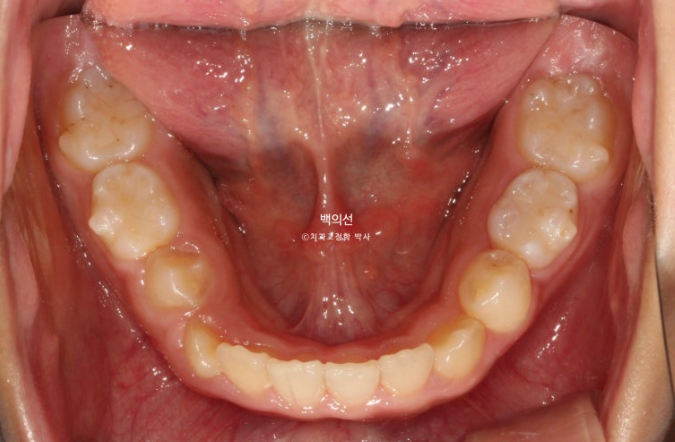

아래도 마찬가지로 악궁확장이 필요합니다.

이 날 공간이 부족하여 앞니가 삐뚤게 나왔고 곧 나올 송곳니는 공간이 부족하여 덧니로 나올 상황입니다.